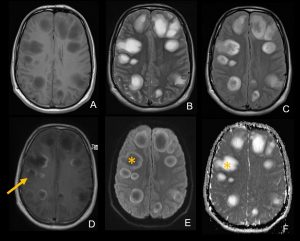

- RM T1 axial B. RM T2 axial C. RM FLAIR axial D. RM T1 axial con contraste E y F. RM DIFUSIÓN axial

Múltiples lesiones redondeadas hemisféricas bilaterales cortico-subcorticales y subcorticales, la mayoría de gran tamaño y distribución asimétrica. Se presentan hipointensas en secuencias T1 e hiperintensas en T2 y FLAIR (con periferia más hiperintensa en T1 y más hipointensa en T2). No restringen en secuencia difusión (*) y presentan realce tras la administración de contraste en forma de anillo, algunas de ellas incompleto y abierto hacia la sustancia gris (flecha).